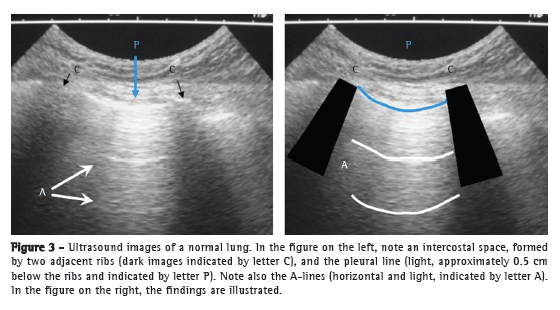

Initially, for B-mode ultrasound, the transducer is positioned with its marker directed to the head of the patient and perpendicular to the ribs, the typical lung ultrasound image being therefore obtained.(4,6) The adjacent intercostal spaces are examined by sliding the transducer vertically (Figure 3).(10)

The ribs block the ultrasound waves and are identified by their posterior acoustic shadowing (letter C in Figure 3), which precludes the visualization of deeper structures. Approximately 0.5 cm below the ribs, a light (hyperechoic) horizontal line, known as the pleural line, is seen (letter P in Figure 3). The pleural line is made up of the visceral and parietal pleura surfaces. During respiration, the two pleural surfaces slide against each other (air displacement), and this appears as a shimmering white line.

The normal lung parenchyma (as well as any anatomical structure filled with gas) cannot be seen beyond the pleura, given that the presence of air prevents ultrasound wave propagation. This generates an artifact known as A-lines, i.e., light (hyperechoic) horizontal lines that are static and repeat at regular intervals (letter A in Figure 3).